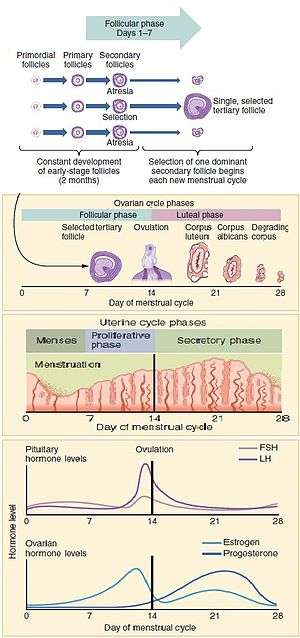

The menstrual cycle is governed by hormonal changes.[6] These changes can be altered by using hormonal birth control to prevent pregnancy.[9] Each cycle can be divided into three phases based on events in the ovary (ovarian cycle) or in the uterus (uterine cycle).[1] The ovarian cycle consists of the follicular phase, ovulation, and luteal phase whereas the uterine cycle is divided into menstruation, proliferative phase, and secretory phase.

Stimulated by gradually increasing amounts of estrogen in the follicular phase, discharges of blood (menses) flow stop, and the lining of the uterus thickens. Follicles in the ovary begin developing under the influence of a complex interplay of hormones, and after several days one or occasionally two become dominant (non-dominant follicles shrink and die). Approximately mid-cycle, 24–36 hours after the luteinizing hormone (LH) surges, the dominant follicle releases an ovocyte, in an event called ovulation. After ovulation, the ovocyte only lives for 24 hours or less without fertilization while the remains of the dominant follicle in the ovary become a corpus luteum; this body has a primary function of producing large amounts of progesterone. Under the influence of progesterone, the uterine lining changes to prepare for potential implantation of an embryo to establish a pregnancy. If implantation does not occur within approximately two weeks, the corpus luteum will involute, causing a sharp drop in levels of both progesterone and estrogen. The hormone drop causes the uterus to shed its lining in a process termed menstruation. Menstruation also occurs in some other animals including shrews, bats, and other primates such as apes and monkeys.[10]

The menstrual cycle can be described by the ovarian or uterine cycle. The ovarian cycle describes changes that occur in the follicles of the ovary whereas the uterine cycle describes changes in the endometrial lining of the uterus. Both cycles can be divided into three phases. The ovarian cycle consists of the follicular phase, ovulation, and the luteal phase whereas the uterine cycle consists of menstruation, proliferative phase, and secretory phase.[1]

Ovarian cycle

Follicular phase

The follicular phase is the first part of the ovarian cycle. During this phase, the ovarian follicles mature and get ready to release an egg.[1] The latter part of this phase overlaps with the proliferative phase of the uterine cycle.

Through the influence of a rise in follicle stimulating hormone (FSH) during the first days of the cycle, a few ovarian follicles are stimulated.[63] These follicles, which were present at birth[63] and have been developing for the better part of a year in a process known as folliculogenesis, compete with each other for dominance. Under the influence of several hormones, all but one of these follicles will stop growing, while one dominant follicle in the ovary will continue to maturity. The follicle that reaches maturity is called a tertiary, or Graafian, follicle, and it contains the ovum.[63]

Ovulation

Ovulation is the second phase of the ovarian cycle in which a mature egg is released from the ovarian follicles into the oviduct.[64] During the follicular phase, estradiol suppresses production of luteinizing hormone (LH) from the anterior pituitary gland. When the egg has nearly matured, levels of estradiol reach a threshold above which this effect is reversed and estrogen stimulates the production of a large amount of LH. This process, known as the LH surge, starts around day 12 of the average cycle and may last 48 hours.[65]

Luteal phase

The luteal phase is the final phase of the ovarian cycle and it corresponds to the secretory phase of the uterine cycle. During the luteal phase, the pituitary hormones FSH and LH cause the remaining parts of the dominant follicle to transform into the corpus luteum, which produces progesterone. The increased progesterone in the adrenals starts to induce the production of estrogen. The hormones produced by the corpus luteum also suppress production of the FSH and LH that the corpus luteum needs to maintain itself. Consequently, the level of FSH and LH fall quickly over time, and the corpus luteum subsequently atrophies.[63] Falling levels of progesterone trigger menstruation and the beginning of the next cycle. From the time of ovulation until progesterone withdrawal has caused menstruation to begin, the process typically takes about two weeks, with 14 days considered normal. For an individual woman, the follicular phase often varies in length from cycle to cycle; by contrast, the length of her luteal phase will be fairly consistent from cycle to cycle.[73]

Uterine cycle

The uterine cycle has three phases.[74]

Menstruation

Proliferative phase

Secretory phase

The secretory phase is the final phase of the uterine cycle and it corresponds to the luteal phase of the ovarian cycle. During the secretory phase, the corpus luteum produces progesterone, which plays a vital role in making the endometrium receptive to implantation of the blastocyst and supportive of the early pregnancy, by increasing blood flow and uterine secretions and reducing the contractility of the smooth muscle in the uterus;[84] it also has the side effect of raising the woman's basal body temperature.[85]